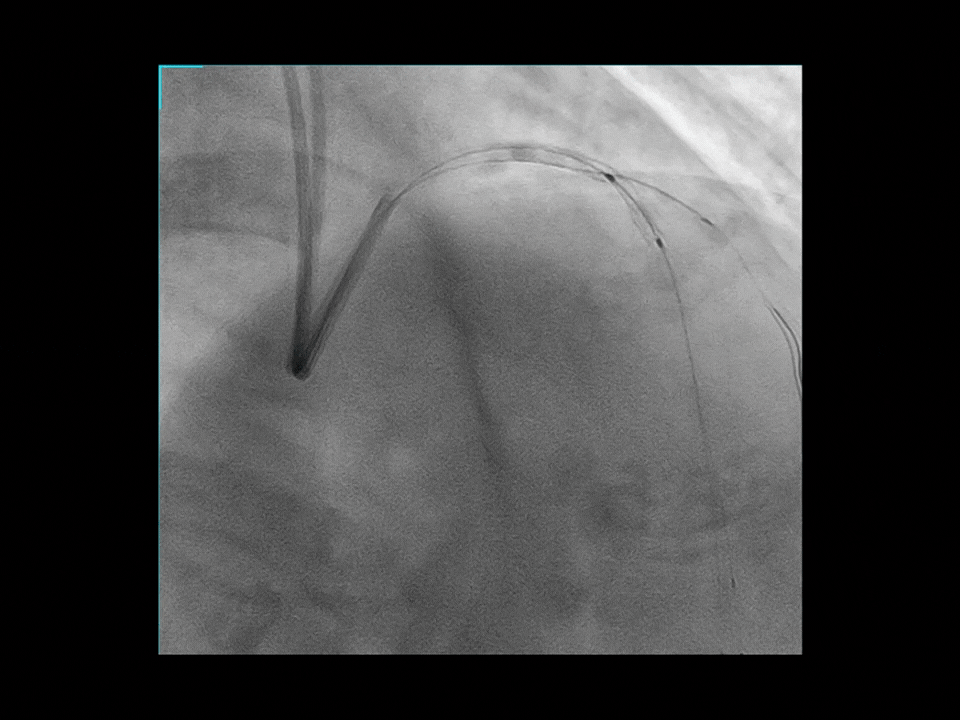

Cardiologie

Îmbunătățire coronariană asistată de AI*

Funcția AI-Enabled Coronary Enhancement oferă imagini clare și consistente, permițând o reducere de până la 50% a dozei de substanță de contrast. Astfel, scade semnificativ riscul de CI-AKI (leziune renală acută indusă de contrast), fără a compromite acuratețea diagnostică.

Hartă coronariană dinamică*

Dynamic Coronary Roadmap (DCR), o tehnologie avansată dezvoltată de UIH, oferă vizualizare în timp real a arterelor coronare, compensând automat mișcarea acestora. Prin suprapunerea angiogramei evidențiate peste imaginile fluoroscopice 2D live, DCR generează o hartă color adaptivă care se ajustează continuu în funcție de mișcarea coronariană. Această ghidare dinamică îmbunătățește precizia și eficiența în navigarea firelor și cateterelor, simplificând procedurile complexe.